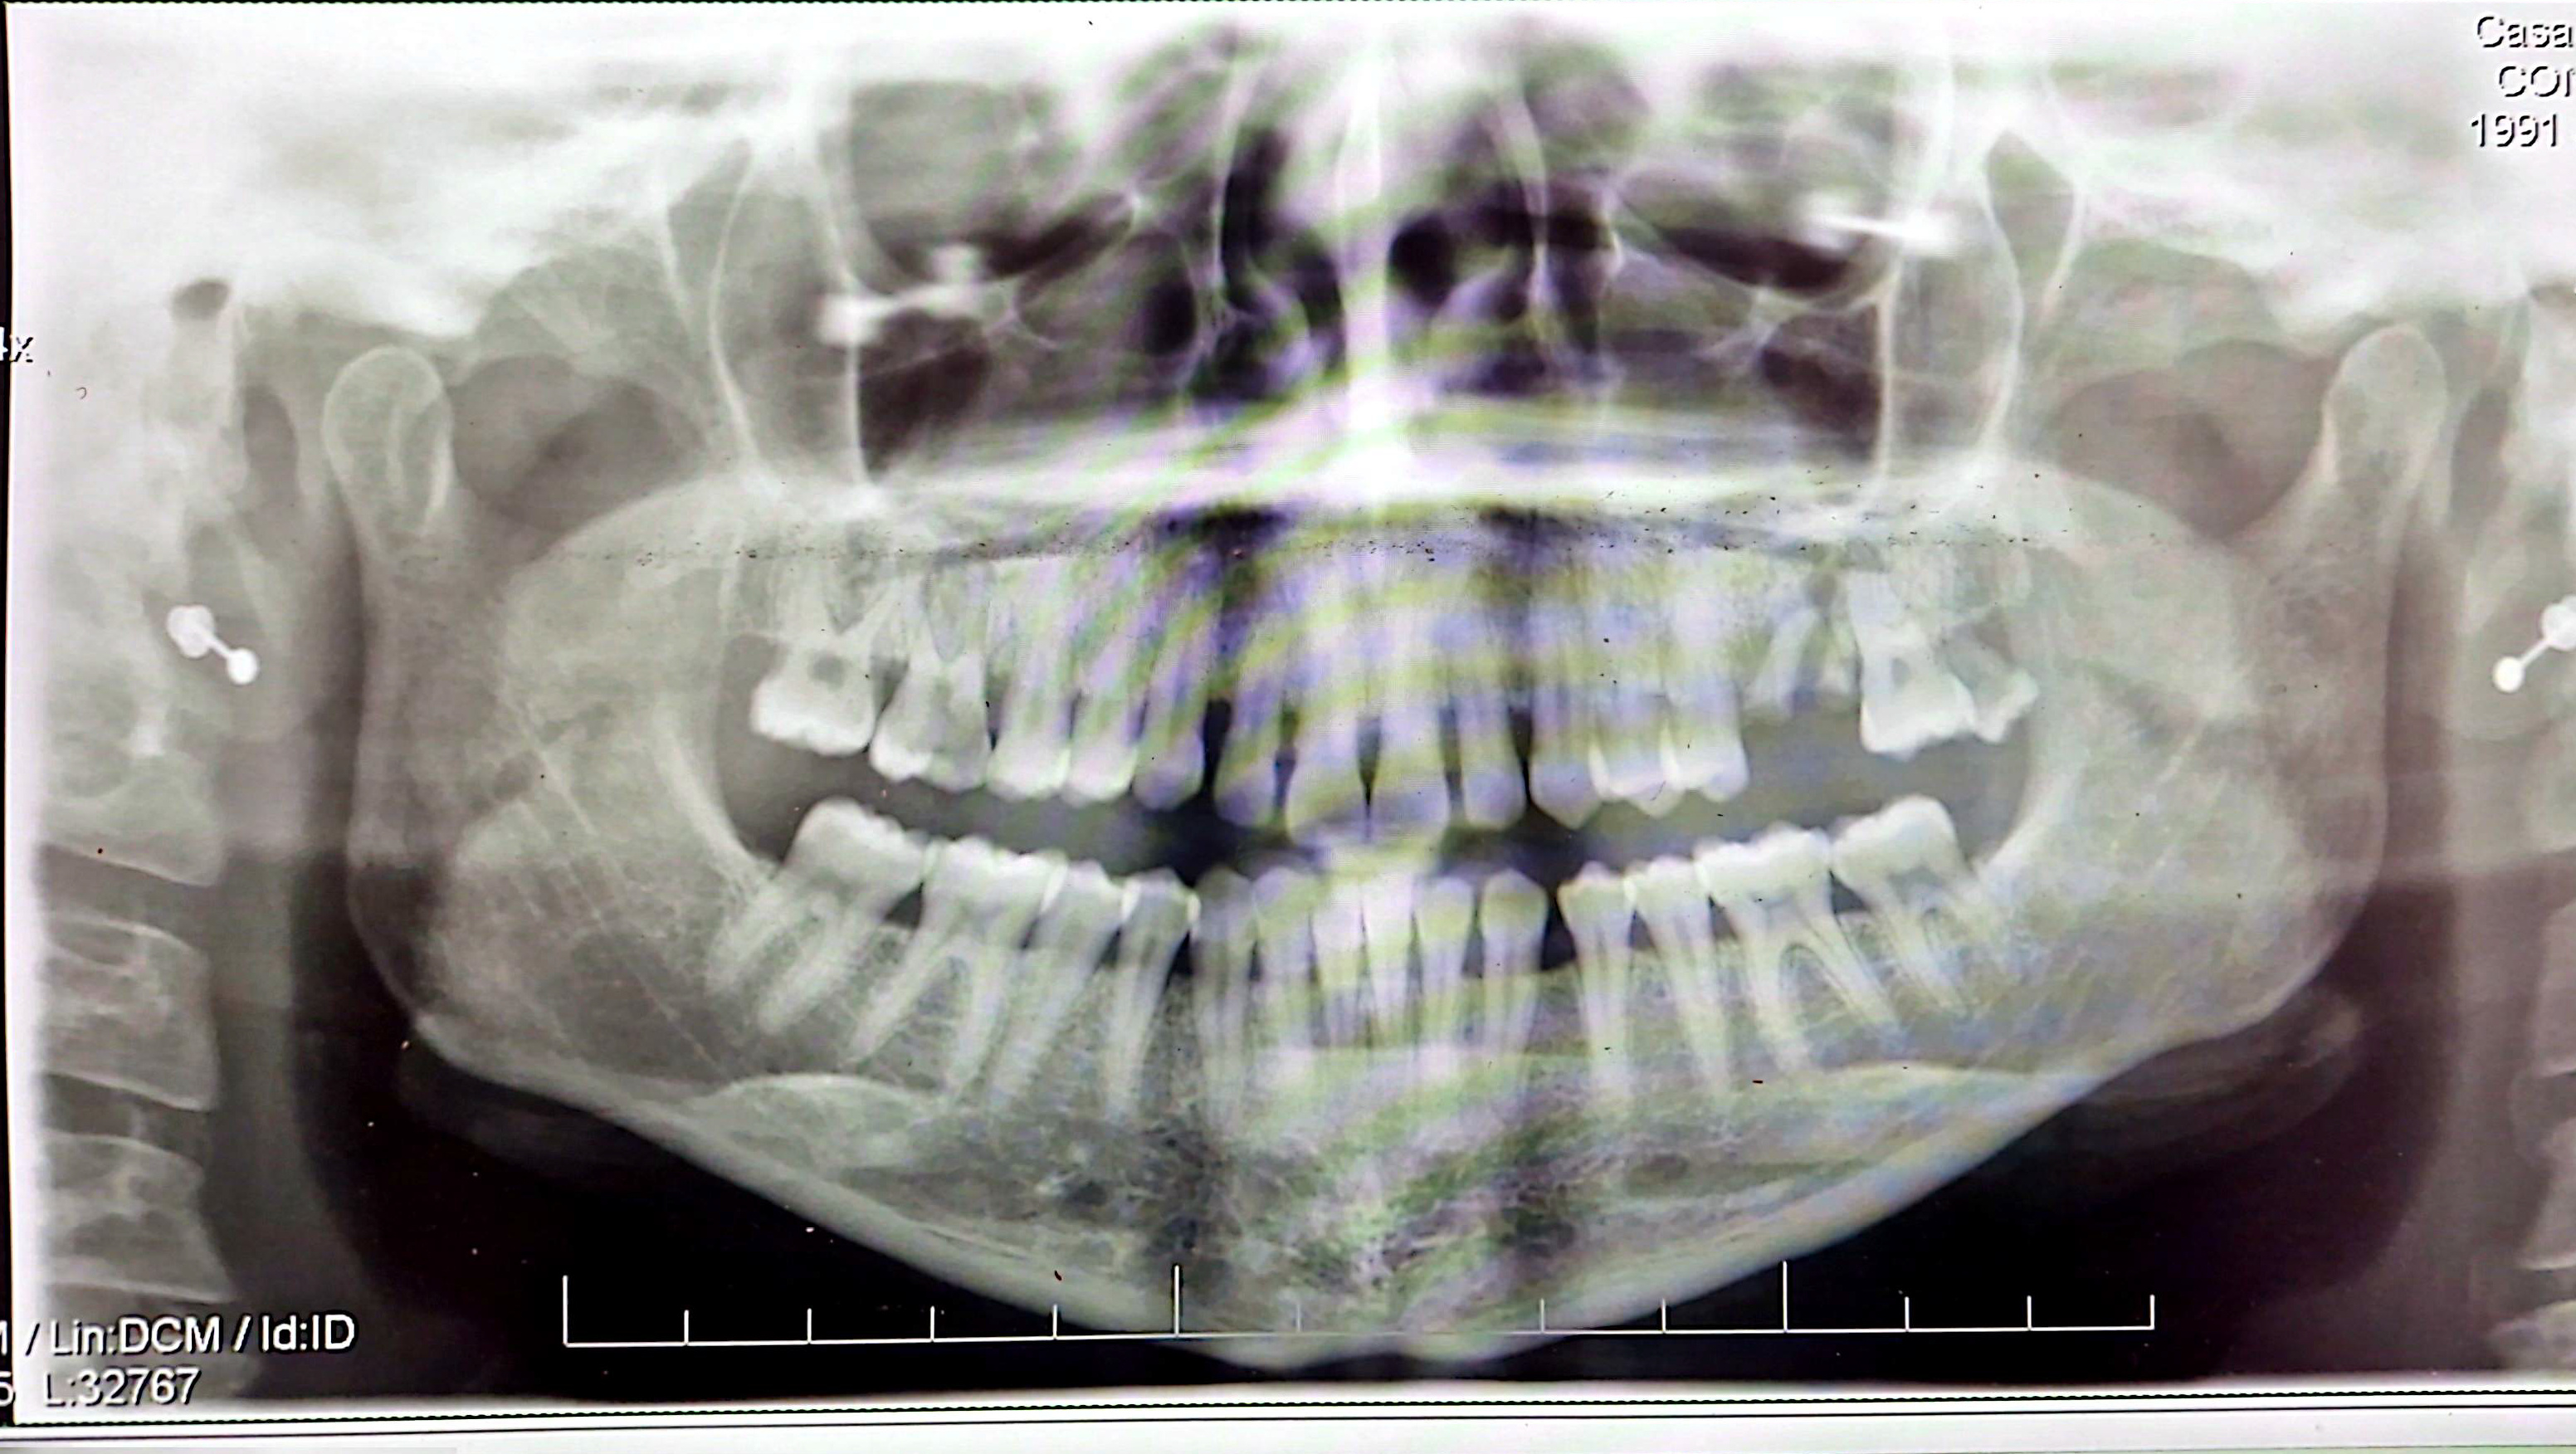

Buon giorno Veronica, il suo quadro clinico è chiaro, presenta l'elemento 28 molto cariato, (dovuto anche all'impossibilità di una corretta pulizia) dell'elemento 26 , non è rimasto più nulla, non presentandosi integro, è irrecuperabile, dubbi potrebbero esserci per la cura del 16, ma l'aspetto clinico, si può valutare con una visita e con un rx endorale quindi si fidi del suo dentista.

No, sono tre denti irrecuperabili.. si fidi del suo dentista - una è una radice - uno è un dente del giudizio che non si sa come sta lì - il 16 è un peccato, ma come si può curare?? si potrebbe tentare, ma ci vogliono tecniche sopraffine..

Due sono da levare, il terzo non è semplice, ma io ci proverei. Potrebbe rivestirlo con un intarsio dopo averlo devitalizzato e ricostruito parzialmente. Certo è una tecnica sofisticata ma da buoni risultati.

Sig. Veronica, la sua odontoiatra la conosce clinicamente, anamnesticamente e radiologicamente; noi non abbiamo riscontri clinici e anamnestici, come possono avere affidabilità le nostre risposte?